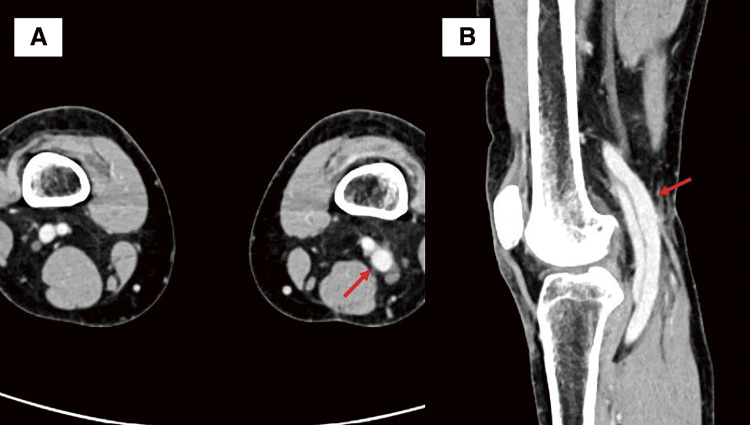

腘静脉动脉瘤(PVA)是一种罕见的血管疾病。我们报告了一例通过进一步评估肺栓塞(PE)导致的心脏骤停(CA)而发现的 PVA 病例。众所周知,PVA 会导致 PE,但很少有 PVA 导致 CA 的报道。医生为患者实施了切向动脉瘤切除术和侧支静脉切开术。患者术后恢复顺利。在进行造影剂增强计算机断层扫描以寻找 CA 的病因时,应考虑到 PVA,因此建议对膝关节以下部位进行筛查。随访1年,未发现并发症。

A popliteal venous aneurysm (PVA) is a rare vascular disorder. We report a case of PVA discovered through further evaluation of sudden cardiac arrest (CA) caused by a pulmonary embolism (PE). It is well-known that PVA causes PE; however, there are few reports of PVA causing CA. A tangential aneurysmectomy and lateral venorrhaphy were performed. The patient's postoperative course was uneventful. When contrast-enhanced computed tomography is performed to search for the cause of CA, PVA should be considered and thus, screening below the knee is recommended. At 1-year follow-up, there were no complications.